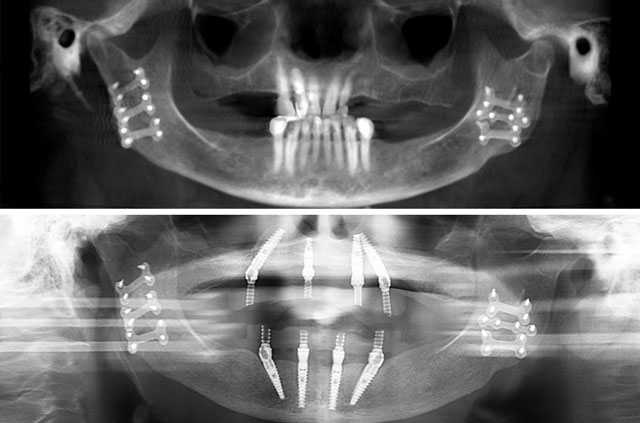

Immediate Implants and Teeth All-On-4 After Jaw Trauma

Patient had a jaw trauma (was broken) before he deside to place dental implants.

During consultation, patient was advised to do All-on-4 Dental Implants and restore with an overdentures same day as surgery.

Surgical Solution

- Bone grafting for both jaws

- All-on-4 Teeth-In-A-Day™ Surgical Solution

Through this technique, was restored esthetic and function on the broken jaw.